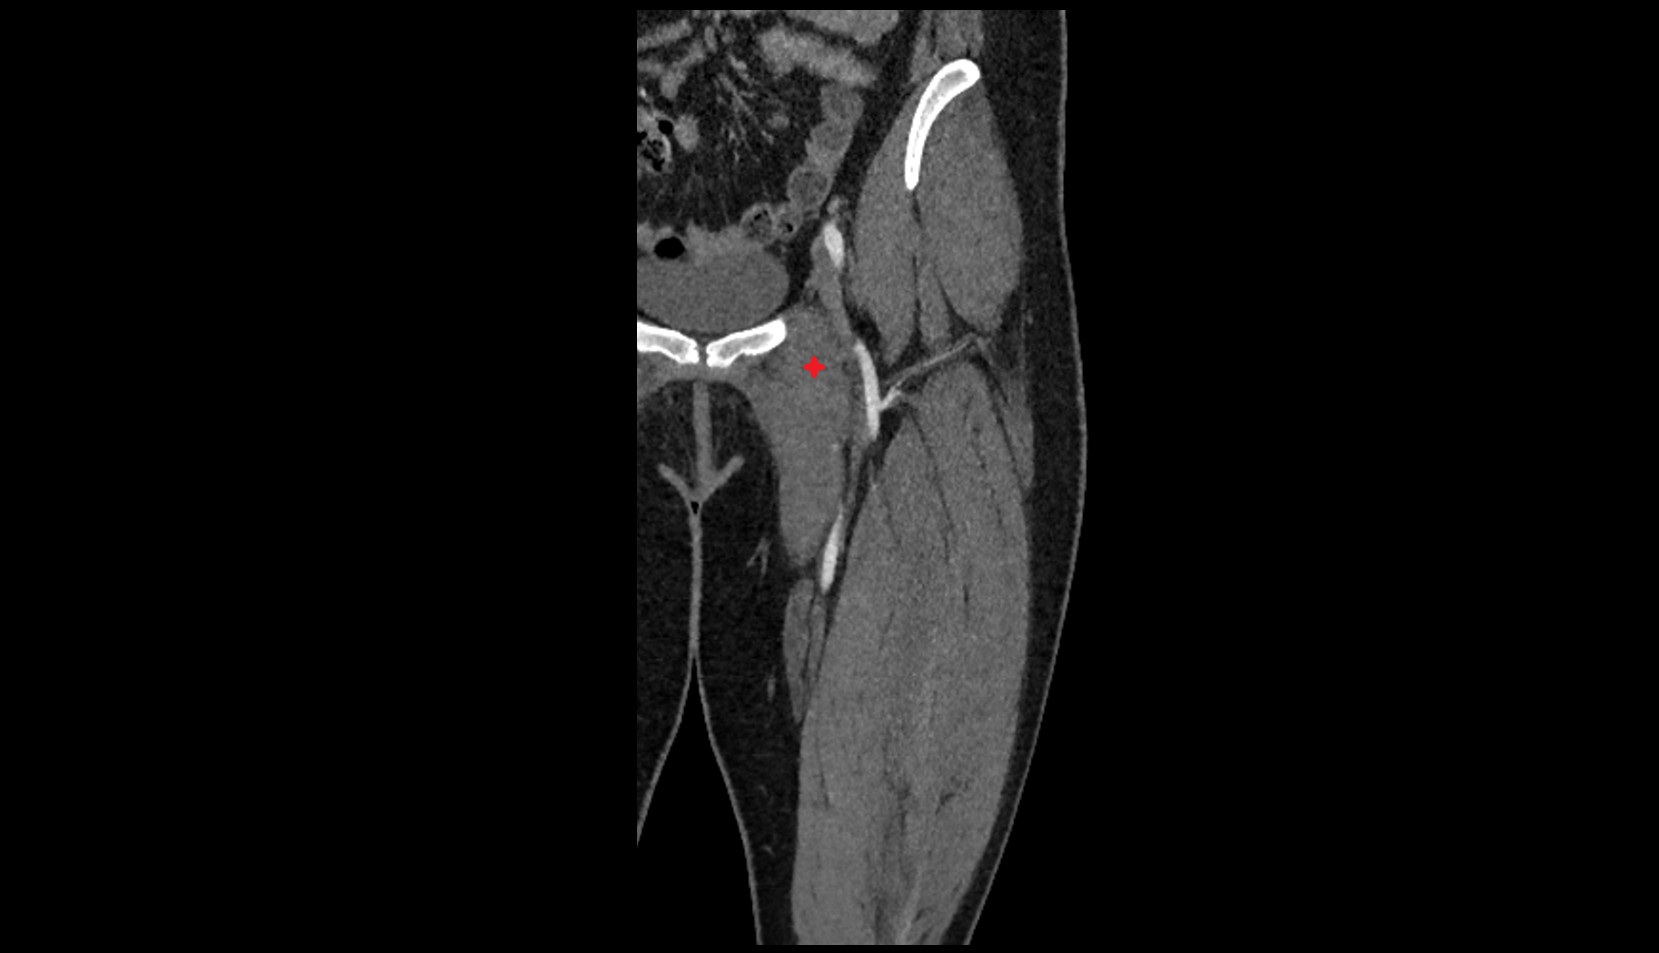

- External iliac artery

- Femoral artery

- Internal iliac artery

- Superficial femoral artery